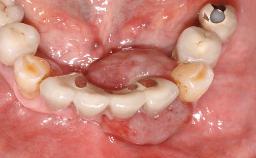

A 24-year-old female patient was treated with an implant- supported crown for single-tooth replacement at site 11. A Straumann Bone Level RC implant (Institut Straumann AG, Basel, Switzerland) was placed with simultaneous bone augmentation, and the periimplant emergence profile was conditioned with a fixed implant-supported provisional crown. After finalization of the mucosal architecture, the clinical situation was transferred by means of a custom impression post for fabrication of an implant-supported screw-retained onepiece crown consisting of a CARES® zirconia abutment (Straumann) with a direct ceramic veneer.